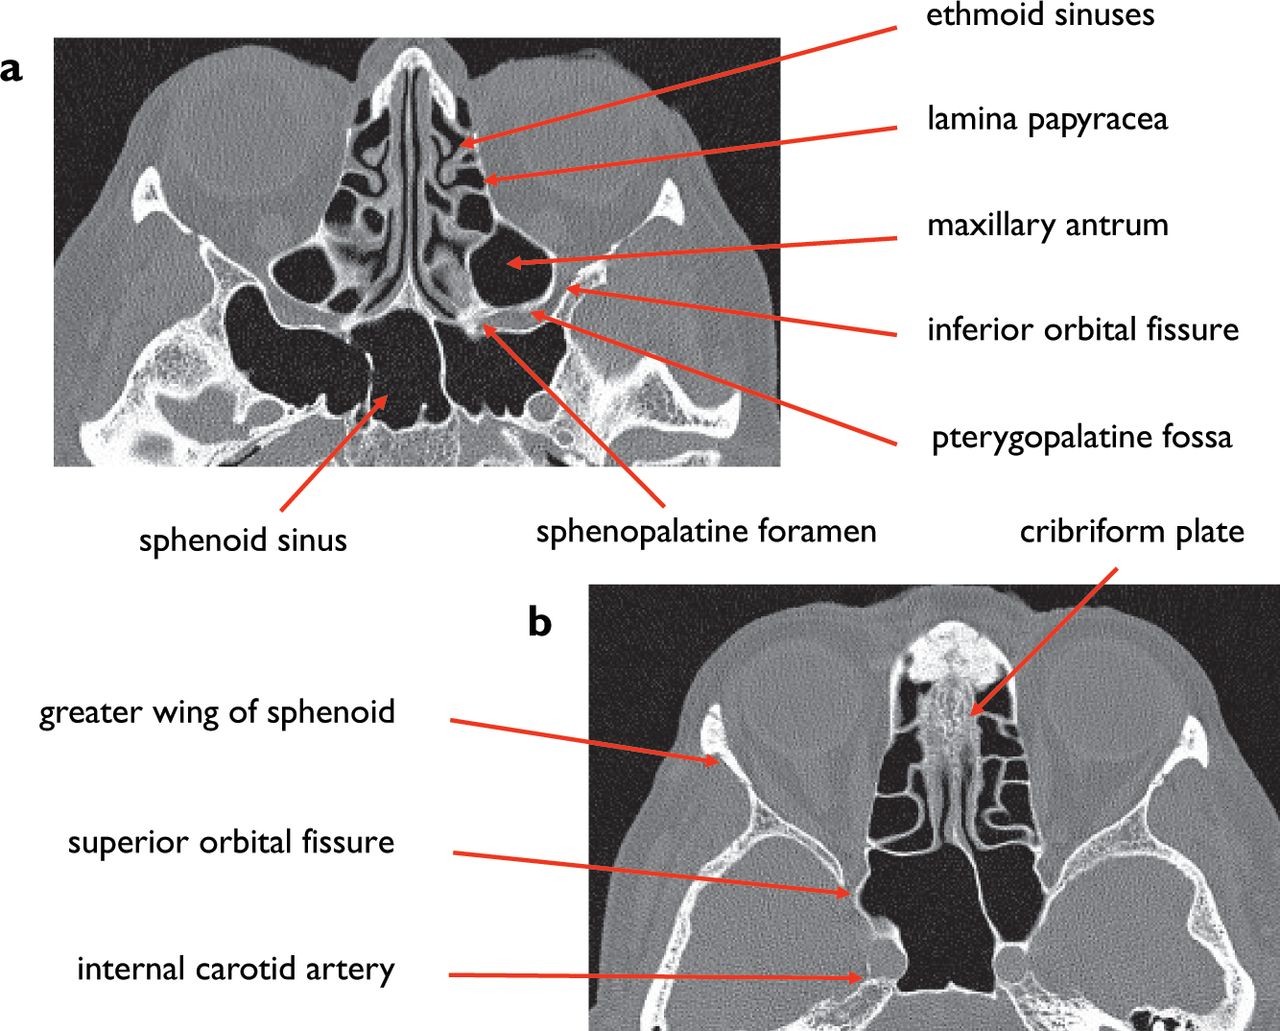

Ct skull base anatomy. You can however go directly to any section using the links below. B axial ct image with color coded overlay shows the skull base bones. The skull base can be evaluated by computed tomography ct which will demonstrate the bony structures of the skull base with its foramina and fissures for vessels and cranial nerves the temporal bone and sinonasal cavities.

Ct anatomy of skull base. Blue central skull base csb purple posterior skull base teal anterior skull base asb. Foramina of the skull base and the structures that pass through them.

Cranial foramina for further details. A axial three dimensional reconstructed ct image with color coded overlay shows the skull base sections. Ct anatomy of skull base.

Blue temporal bones fuchsia nasal bones green ethmoid bone light pink vomer purple occipital bones teal sphenoid bone yellow zygomatic bones. Basic anatomy review the bones sutures and fissures that comprise the skull base. Detailed anatomy enter this module for a more detailed review of skull base anatomy.

The base of the skull is perforated by numerous foramina which allow vessels and nerves to pass through the base of the skull allowing the intracranial cavity to communicate with the rest of the body see main article. Skull ct anatomy the sagittal suture is the line where the right and left parietal bone are in contact. A noncontrast sinus or skull base ct which covers the mastoids temporal bone and entire skull base is recommended and intravenous contrast is not usually necessary as the mri will provide soft tissue detail.

Ct is more sensitive in detecting fibro osseous skull base lesions calcification and sclerosis. The module interface is meant to mimic a radiology workstation with adjacent image scrolling via arrow keys and or mouse wheel button. Navigating the skull base identify the petro occipital fissure to navigate the major structures of the skull base.